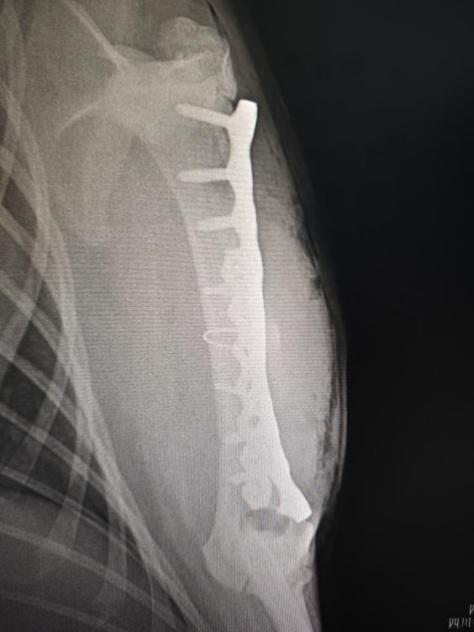

手术后左前肢腹背位X光

手术团队由德赢VWIN官方网站教学动物医院院长沈留红、动物外科专家石先鹏、动物内科专家巫晓峰、医生陈善瑜和罗皓、麻醉医生邓聪辉、手术助手王郡东、助理唐清婷、张涵艺、钱琳、王均、李鑫等组成,并与动物园动物疾病预防组刘俊卿副经理团队一道组成会诊专家组,确定麻醉和手术方案。外科专家石先鹏凭借丰富的经验和精湛的技术,对水豚肱骨进行了精确的复位和固定。手术全程在严格的无菌条件下进行,确保了安全性和成功率。

术后恢复期,医疗团队将对水豚进行严密观察和专业护理。专家表示,尽管手术已经成功完成,但水豚的康复之路仍需时间和耐心。将持续监测其恢复情况,并提供必要的营养和医疗支持。